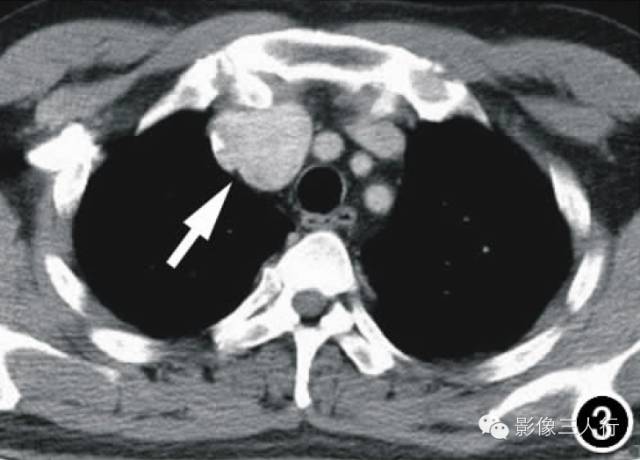

图1横轴面CT平扫示前上纵隔偏右侧一团块影(箭),大小约3.5cmX3.2cm,边界尚清,密度均匀,CT值约44HU,局部血管受压推移。图2横轴面CT增强扫描动脉期示肿块显著均匀强化(箭),CT值为95HU。图3横轴面CT增强扫描延迟期示肿块持续强化(箭),CT值为158HU。图4镜下示细胞排列呈编织状、旋涡状,疏密不均,细胞呈梭形、短圆形,胞核红染,部分细胞出现不典型增生(X400,HE)。